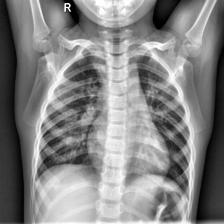

Coronavirus Disease 2019 (COVID-19) demonstrated the need for accurate and fast diagnosis methods for emergent viral diseases. Soon after the emergence of COVID-19, medical practitioners used X-ray and computed tomography (CT) images of patients' lungs to detect COVID-19. Machine learning methods are capable of improving the identification accuracy of COVID-19 in X-ray and CT images, delivering near real-time results, while alleviating the burden on medical practitioners. In this work, we demonstrate the efficacy of a support vector machine (SVM) classifier, trained with a combination of deep convolutional and handcrafted features extracted from X-ray chest scans. We use this combination of features to discriminate between healthy, common pneumonia, and COVID-19 patients. The performance of the combined feature approach is compared with a standard convolutional neural network (CNN) and the SVM trained with handcrafted features. We find that combining the features in our novel framework improves the performance of the classification task compared to the independent application of convolutional and handcrafted features. Specifically, we achieve an accuracy of 0.988 in the classification task with our combined approach compared to 0.963 and 0.983 accuracy for the handcrafted features with SVM and CNN respectively.